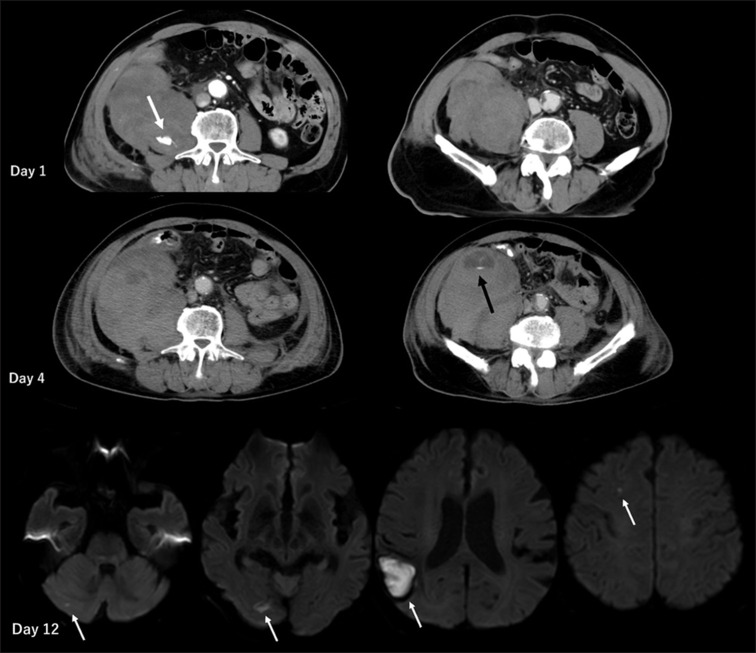

Multiple Cerebral Infarctions after Treatment of Acquired Factor XIII Deficiency with Retroperitoneal Hematoma.

用腹膜后血肿治疗获得性因子 XIII 缺乏症后的多发性脑梗塞。